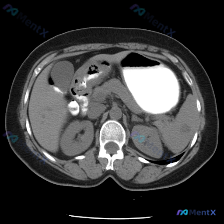

今天看到一份腹部CT影像的分析,最初的疑问是「脾脏病变」,但看完整个报告觉得读片思路的纠偏比诊断本身更有意义,整理一下和大家分享。 先看完整影像情况 图像层面:上腹部横断面,包含胃体、肝、胆囊、脾及双肾上极水平;图像清晰度良好,无明显伪影,软组织结构辨识度可。胃腔内有高密度造影剂或内容物,肝及腹部血...